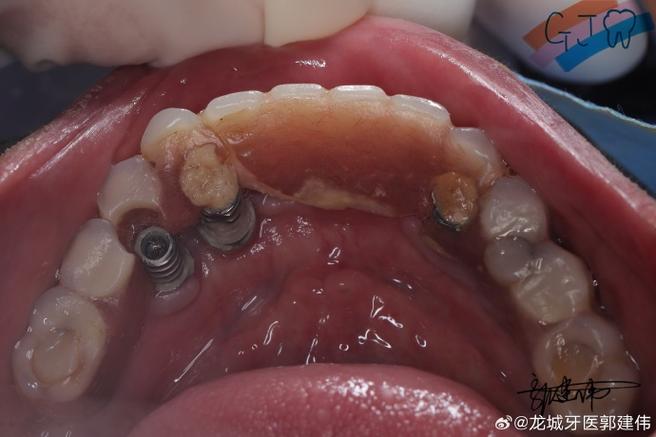

- 检查种植体基台:确认基台是否在位、是否松动、是否损坏、连接螺纹是否完好。

- 检查种植体:轻轻晃动种植体,评估其稳定性(排除种植体松动)。

- 拍X光片:通常需要拍摄根尖片或全景片,观察种植体周围骨情况、基台位置、牙冠与基台密合度等。